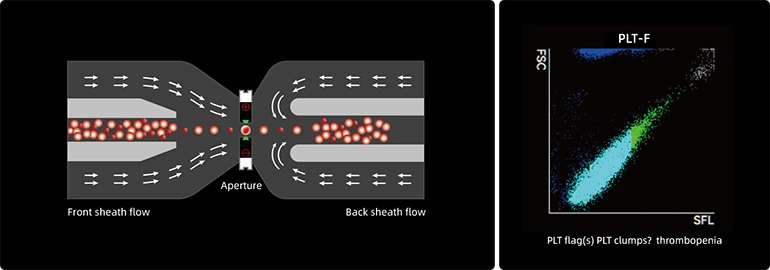

Комплексное решение для PLT

- Новый метод измерения импеданса потока в оболочке снижает помехи, создаваемые микроцитами и крупными тромбоцитами.

- Специальная технология разрушения агрегатов тромбоцитов значительно улучшает агрегацию тромбоцитов.

- Мощный канал PLT-F дополнительно предотвращает помехи, создаваемые клеточными остатками.